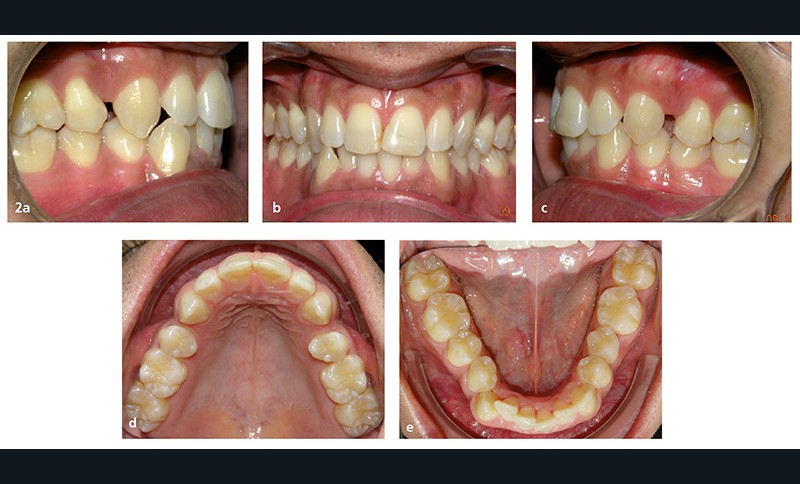

La demande du patient est d’aligner ses dents de l’arcade mandibulaire et de fermer les espaces résiduels d’extraction au maxillaire (fig. 2a à e). Ses fréquents déplacements professionnels à l’étranger, durant chaque fois plusieurs mois, ne lui permettent pas des rendez-vous réguliers au cabinet.

Sur le plan dentaire, dans le sens sagittal, il existe une classe II molaire thérapeutique et une classe I canine avec des espaces résiduels d’extractions en distal des canines chiffrés à 1,5 mm à droite et 2,5 mm à gauche. Les rebords des 11 et 21 ont été fracturés et reconstitués au composite (fig. 2a à e).

À la mandibule, la DDM est chiffrée à 4 mm environ ; 43 est en mésiovestibuloposition et en occlusion en bout à bout avec 12 ; 42 est en linguoposition, 35 en rotation axiale mésiolinguale ; 44 présente une anomalie de forme avec un diamètre mésiodistal augmenté et vestibulolingual diminué (dysharmonie dento-dentaire).